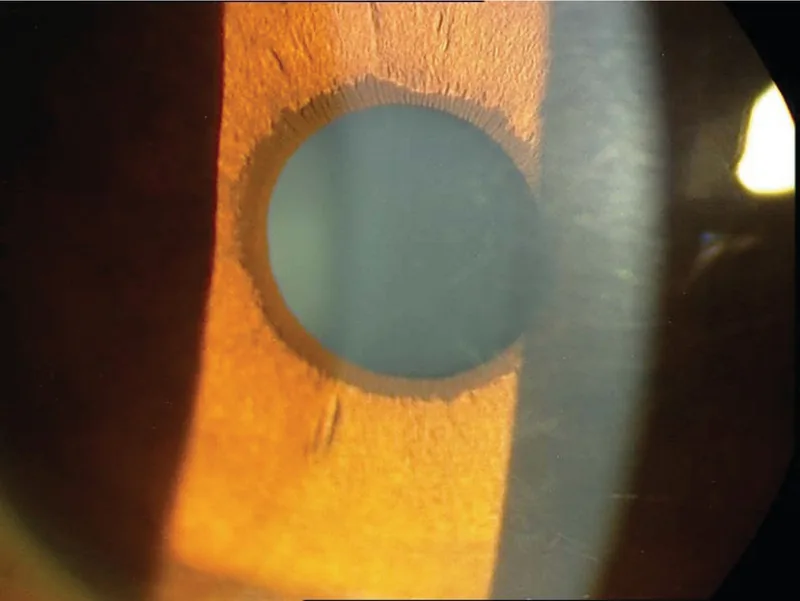

Section titled “1. 後天性ぶどう膜外反とは”後天性ぶどう膜外反(acquired ectropion uveae:AEU)は、虹彩色素上皮が虹彩の前表面へ脱出または突出する病態である。後天性虹彩外反(acquired iris ectropion)とも呼ばれる。瞳孔付近に好発するが、虹彩の他の部位にも生じうる。

Section titled “細隙灯顕微鏡所見”- 瞳孔縁の色素変化:分節状の色素沈着から、瞳孔周囲を完全に取り囲む平坦な色素環まで多様

- 瞳孔変形(瞳孔偏位):牽引による形状・大きさの歪み

Section titled “4. 診断と検査方法”- 細隙灯顕微鏡検査:虹彩前面の色素上皮脱出、瞳孔変形、虹彩前面の膜状組織を確認

線維血管膜形成による牽引機序

Section titled “線維血管膜形成による牽引機序”虹彩の前表面に**収縮性の線維血管膜(fibrovascular membrane)**が形成されることが中心的な機序である。この膜が瞳孔縁周囲の後方色素上皮・虹彩括約筋・虹彩実質を前面へ牽引し、巻き込ませる(tractional curling)。同時に線維柱帯を被覆・閉塞させ、眼圧上昇を引き起こす。